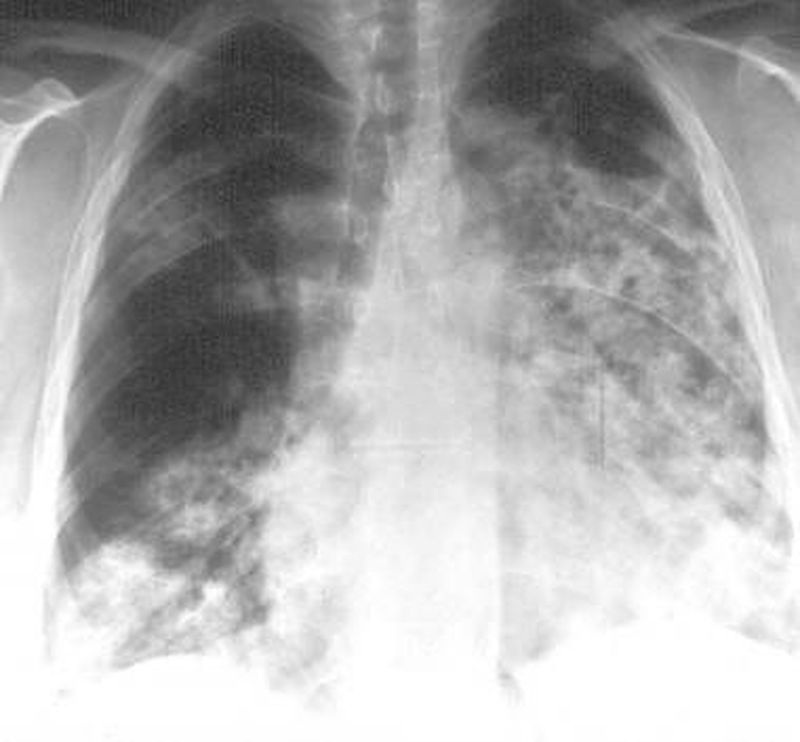

Can some one describe the radiological findings in this chest x ray , please